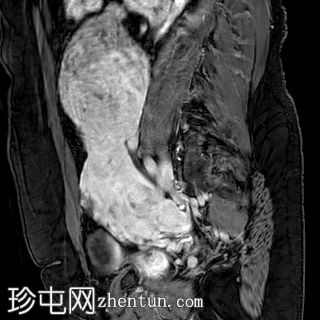

矢状位T1加权像

增强脂肪抑制像

4.jpg

增强扫描图像显示,与其他肌瘤相比,该病灶呈异质性强化,强化区域混杂,中心大片区域无强化(与T2加权像上的囊性区域相对应)。

病例讨论

在原有肌瘤内快速生长出一个体积较大、异质性且伴有囊性/坏死区域的病灶,高度怀疑为子宫平滑肌肉瘤。

遗憾的是,患者病情严重,无法进行进一步检查,因此无法通过病理学确诊。